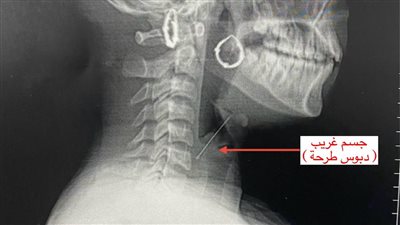

إنقاذ حياة فتاة ابتلعت "دبوس طرحة" بمستشفى بنها الجامعي

الثلاثاء 28/مارس/2023 - 03:50 م